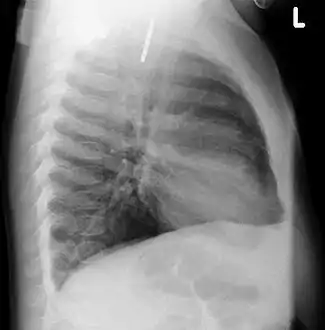

AP X ray showing a 9mm battery in the intestines

Lateral X ray showing a 9mm battery in the intestines